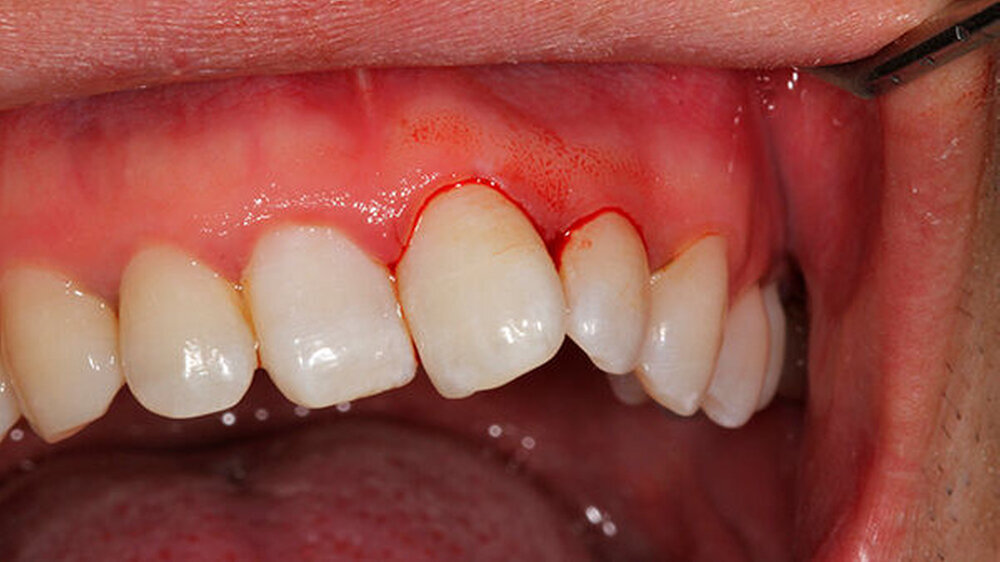

Oralchirurg Marcus Stoetzer arbeitete drei Monate lang im Feldlager der Bundeswehr in Mazar e Sharif - insgesamt behandelte er in Afghanistan 298 Soldaten. Die Bilder zeigen, aus welchem Grund sie zu ihm kamen.